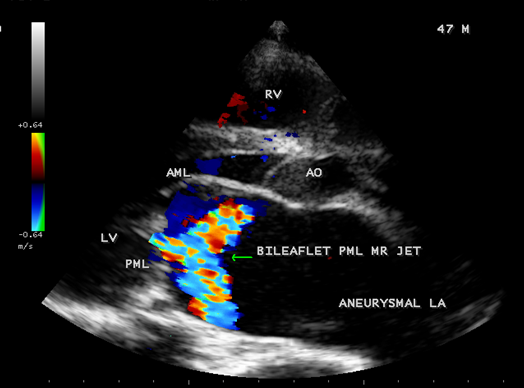

Case 2. PML (posterior mitral leaflet) prolapse causing severe mitral regurgitation with aneurysmal LA (left atrium) as shown in Figures 3 to 8 due to PML chordal rupture of rheumatic etiology in a 47- year old male. Patient was advised lifelong penicillin prophylaxis and MVR (mitral valve replacement).

Figure 5. Parasternal long axis view showing the ‘bileaflet’ MR (mitral regurgitation) jet originating from PML (posterior mitral leaflet) in a 47-year-old male.

Figure 6. Parasternal long axis view showing the ‘bileaflet’ mitral regurgitation due to PML chordal rupture in a 47- year old male.